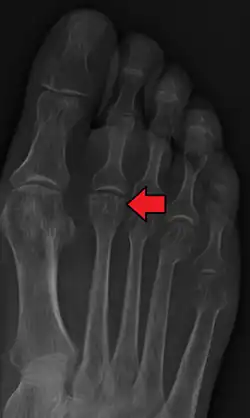

- Radiography: X-rays may reveal flattening, sclerosis, or fragmentation of the metatarsal head.